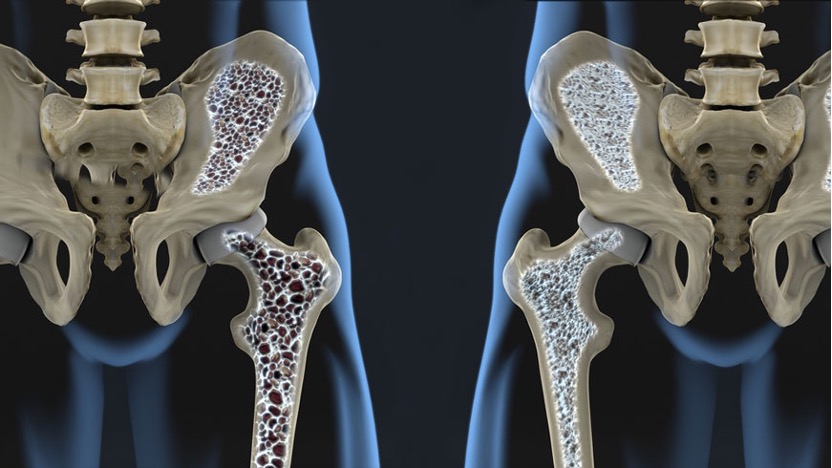

2️⃣ 骨頭結構從「蜂巢」變成「中空脆裂」

健康骨骼像蜂巢一樣緻密;

骨密度下降後,孔洞變大、結構鬆散,輕微跌倒就可能骨折。

1️⃣ 骨密度越低,骨折風險越高

研究顯示,骨密度每下降 1 個標準差(1 SD),骨折風險會上升約 1.5~2.5 倍。